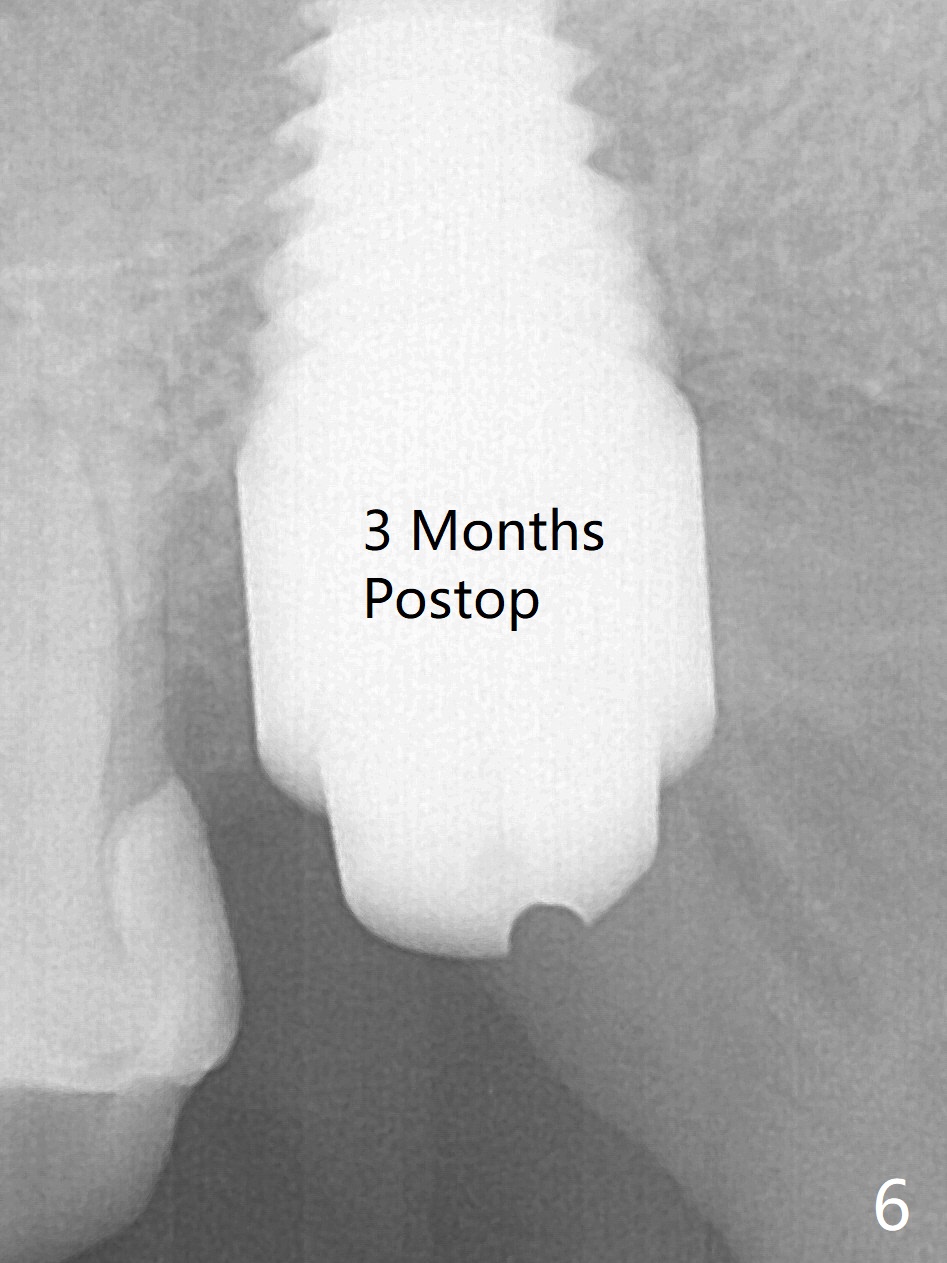

A 56-year-old woman has sign of periimplantitis 2 years 9 months post cementation. After incision, the 5.5x13 mm bone-level implant is ~ 3 mm inferior to the buccal crest. The implant is removed with 7/6 mm trephine bur, elevator and implant driver. The sinus membrane perforates. A 8x17 mm tap achieves stability (Fig.1), but the peripheral bone seems to be thin. Although a 7x14 mm tissue-level implant has stability, it is placed too deep (Fig.2). Following insertion of a piece of Osteogen plug for sinus membrane repair, a 8x14 mm implant is placed with >40 Ncm with allograft placed around the unpolished portion of the implant (Fig.3,4). A 6x3 mm abutment is placed to hold periodontal dressing in place. Because of the abutment with a slot (Fig.5 A), the periodontal dressing remains in place 4 days postop before the patient travels back home for 4 hours. In fact there is no postop sinus infection; the implant threads seems not be exposed 3 months postop (Fig.6). Because of the large implant, it is loaded early (Fig.7, 8 (Temp Bond)). Upper Molar Immediate Implant, Trajectory II 劈开术 Xin Wei, DDS, PhD, MS 1st edition 08/09/2019, last revision 04/11/2021